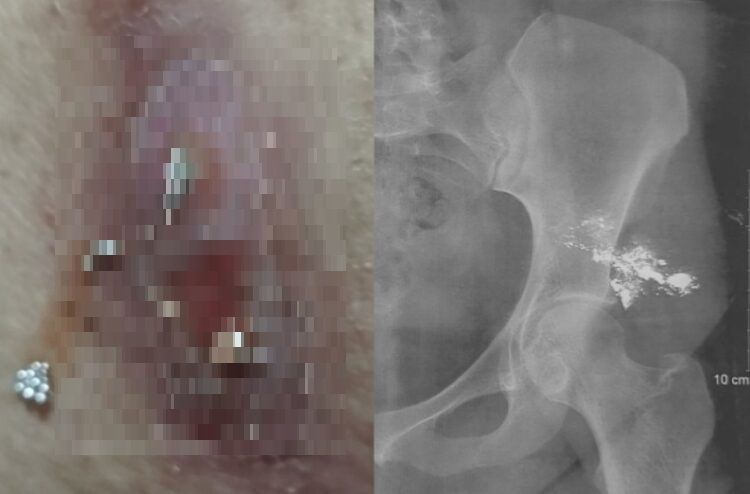

여성 엉덩이 통증을 느낀 부위에서 흘러나온 은색 액체(왼쪽)가 수은으로 밝혀졌다. 오른쪽 사진에서는 여성의 엉덩이에 축적돼 있는 수은이 선명하게 보인다. 사진=Clilnical Case Reports

로그만 하킴 병원 의료진은 검사결과 A씨의 피부 병변에는 은색 액체가 들어있었고, 붉은색을 띄고, 압통이 있는 상태였다고 진단했다. 또한 A씨의 방사선 사진 촬영 결과, 엉덩이 왼쪽에 방사선이 투과하지 못하는 물질이 다량 축적돼 있는 것을 발견했다.